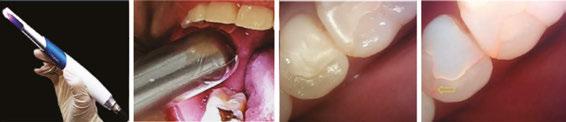

An innovative diagnostic method that addresses these clinical concerns through digital data is based on Quantitative Light-induced Fluorescence (QLF) (Q-ray system, AIOBIO, Seoul, South Korea). QLF utilizes blue visible light at a wavelength of 405 nm to illuminate the tooth surface: healthy regions of the tooth exhibit green fluorescence, while regions with demineralization (such as early carious lesions), micro-cracks, or accumulations of bacterial metabolites display either loss of fluorescence or red fluorescence due to scattered light. These subtle fluorescence patterns are quantitatively represented as ΔF (indicating mineral loss) and ΔR (representing porphyrin-based bacterial metabolites), providing numerical data for objective assessment.

Based on this principle, this technology enables real-time and repeated detection of otherwise hidden lesions during orthodontic treatment. For example, white spot lesions that appear around brackets — indicators of initial demineralization which may be missed by visual inspection or clinical experience alone — can be detected at an early stage, as the ΔF value exceeds a defined threshold. Similarly, interproximal caries, which are traditionally undetectable without bitewing radiographs, can be precisely identified by Q-ray even when mineral loss is less than 6%. Most importantly, micro-cracks in teeth, which are almost impossible to detect visually or radiographically during orthodontic treatment, can be visualized, with the location, depth, and bacterial activity of the lesion clearly displayed via ΔF, ΔR values, and fluorescence imaging — crucial information for prognosis and treatment planning.

Figure 1: Early interproximal carious lesions and areas of plaque accumulation are not visually detectable in a patient with labial bracket placement. Providing these visualized images to the patient can serve as an effective tool for motivating oral hygiene practices and accurately informing them of the potential risk for dental caries development

of its key strengths lies in enhancing communication between patients and practitioners. All examination outcomes are stored as photographic images, color-mapped graphics, and quantitative data, enabling visualization of lesion changes over time — from the initiation of orthodontic treatment, through interim monitoring, to post-removal of appliances. As a result, patients are not merely given fleeting verbal explanations but are presented with objective data on the status of their teeth, which strongly motivates them toward improved oral hygiene and increases their engagement with the treatment process. The images above present Q-ray scans from patients with labial and lingual bracket attachments. Presenting such imagery to patients not only underscores the importance of oral hygiene, increasing the educational effect, but also provides objective evidence that may protect clinicians in the event of dental caries or other complications arising during orthodontic treatment.

Figure 2: In a patient with lingual bracket placement, early interproximal carious lesions and plaque accumulation are detectable on the lingual surfaces with brackets, despite the absence of visible abnormalities on the labial surfaces. This finding highlights the importance of targeted oral hygiene education for lingual orthodontic patients, emphasizing the management of visually inaccessible risk sites to prevent caries development

Figures 3A-3B: Pre-orthodontic crack assessment was conducted using Q-ray Cam and Q-ray PenC. 3A. In a 20-year-old female patient, frontal intraoral imaging with Q-ray Cam detected a crack on the maxillary left central incisor. Consequently, orthodontic appliance placement was postponed and limited to an 8-month duration. 3B. Q-ray PenC allowed precise evaluation of the posterior molars, revealing a clear crack line in a clinically intact restored molar not detectable by conventional visual inspection